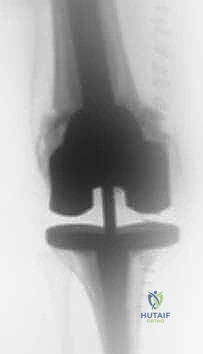

جراحة مراجعة مفصل الركبة الكلي: التغلب على فقدان عظم الفخذ باستخدام الدعامات والطعوم العظمية

جراحة مراجعة مفصل الركبة الكلي هي إجراء متخصص يُعالج فشل المفصل الصناعي السابق وفقدان العظم، خاصة في عظم الفخذ. يتضمن العلاج استخدام دعامات معدنية أو طعوم عظمية لاستعادة بنية المفصل ووظيفته، ويُعد الأستاذ الدكتور محمد هطيف الرائد في هذا المجال بصنعاء.

الخلاصة الطبية السريعة: جراحة مراجعة مفصل الركبة الكلي (Revision Total Knee Arthroplasty) هي إجراء جراحي معقد ومتخصص للغاية، يهدف إلى علاج فشل المفصل الصناعي السابق والتغلب على التحديات التشريحية الناتجة عن فقدان العظم، وتحديداً في عظم الفخذ (Femur). يتطلب هذا الإجراء استخدام تقنيات متقدمة مثل الدعامات المعدنية المعيارية (Modular Augments)، المخاريط (Cones)، والطعوم العظمية (Bone Grafts) لاستعادة بنية المفصل، خط المفصل الطبيعي، والميكانيكا الحيوية للركبة.

إن جراحة المراجعة ليست مجرد تكرار للجراحة الأولى؛ بل هي تحدٍ جراحي وهندسي من الطراز الأول. التحدي الأكبر والأكثر تعقيداً الذي يواجه الجراح في هذه العمليات هو "فقدان العظم" (Bone Loss)، خاصة في الجزء السفلي من عظم الفخذ (Distal Femur). عندما يتآكل العظم المحيط بالمفصل القديم، يترك وراءه فجوات وتجاويف تجعل من المستحيل تثبيت مفصل جديد بالطرق التقليدية.

في الجراحة الأولية، يتم قطع جزء بسيط من هذا العظم لتلبيس المفصل الصناعي. ولكن عند فشل المفصل، يحدث تدمير للبنية العظمية (Metaphysis and Epiphysis)، مما يفقد المفصل الجديد نقاط الارتكاز الأساسية. استعادة "خط المفصل الطبيعي" (Joint Line) هو السر وراء نجاح جراحة المراجعة، وهو ما يتطلب مهارة استثنائية من الجراح لتعويض هذا النقص العظمي بدقة مليمترية.